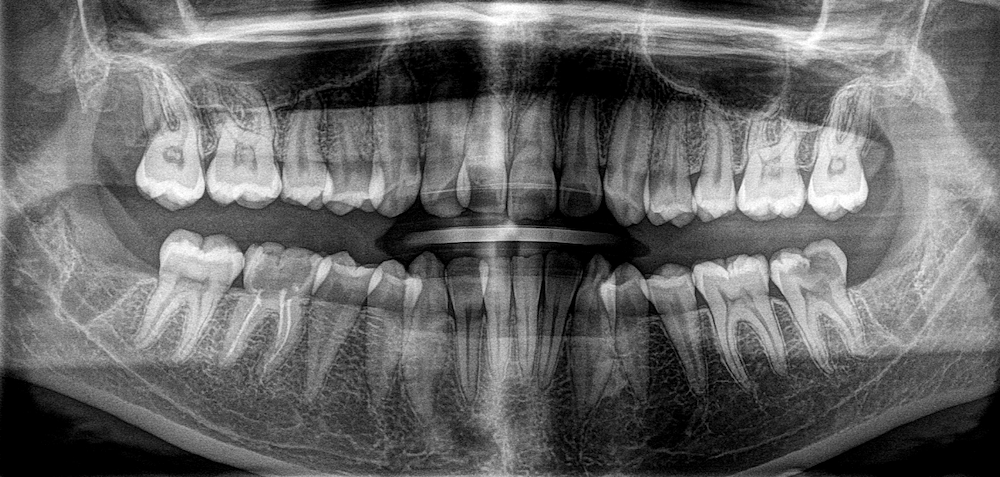

Під час огляду та рентгенологічної діагностики лікарка побачила всі чотири зуби мудрості. Вони ще не були повністю сформовані, але вже мали положення, яке потенційно могло ускладнювати ортодонтичне лікування і вимагало окремої оцінки перед початком лікування.

- На верхній щелепі зуби мудрості ще були на ранній стадії розвитку: коронкова частина вже сформувалась, а корені ще ні.

- На нижній щелепі корені вже формувались активніше, але ще не були повністю завершені.

Саме такий період часто є більш сприятливим для видалення: зуб уже можна чітко визначити на знімку, але корені ще не стали довгими й складними за формою. Це може зробити втручання менш травматичним і більш прогнозованим.